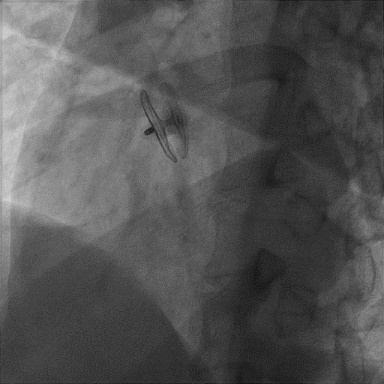

Case 3

卵圆孔隧道长4.4mm,裂隙直径1.7mm。可见房水平右向左分流。应用D-shufo 2424-3 PFO封堵器成功封堵